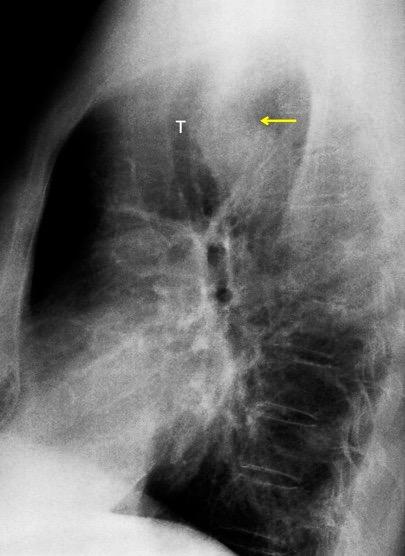

Raro. (2-9% de los T. tímicos). Asintomático. Contiene grasa (hasta 90%) y tejido timico (10-33%). Pueden ser muy grandes y confundirse con cardiomegalia. La tomografía “clásica” muestra los límites de la silueta cardiaca. (flechas)

Líneas paraespinales formando un “paréntesis” por encima del diafragma. El signo señala el origen “intratorácico” de la lesión.

Conrad A et al. Pott’s disease associated with large and multiple abscesses in a 30-year-old migrant from Chad. BMJ Case Rep 2018

(lesiones toracoabdominales) La divergencia de las líneas paraespinales apunta a lesión toracoabdominal, que desde el tórax desciende y penetra en el abdomen.

Signo del “iceberg” positivo en Tb vertebral

Afectación por vía hematógena. Región dorsolumbar más frecuente. Afectación inicial: irregularidad de los platillos vertebrales, disminución del disco intervertebral con esclerosis ósea adyacente. Kim. Radiographics.2001